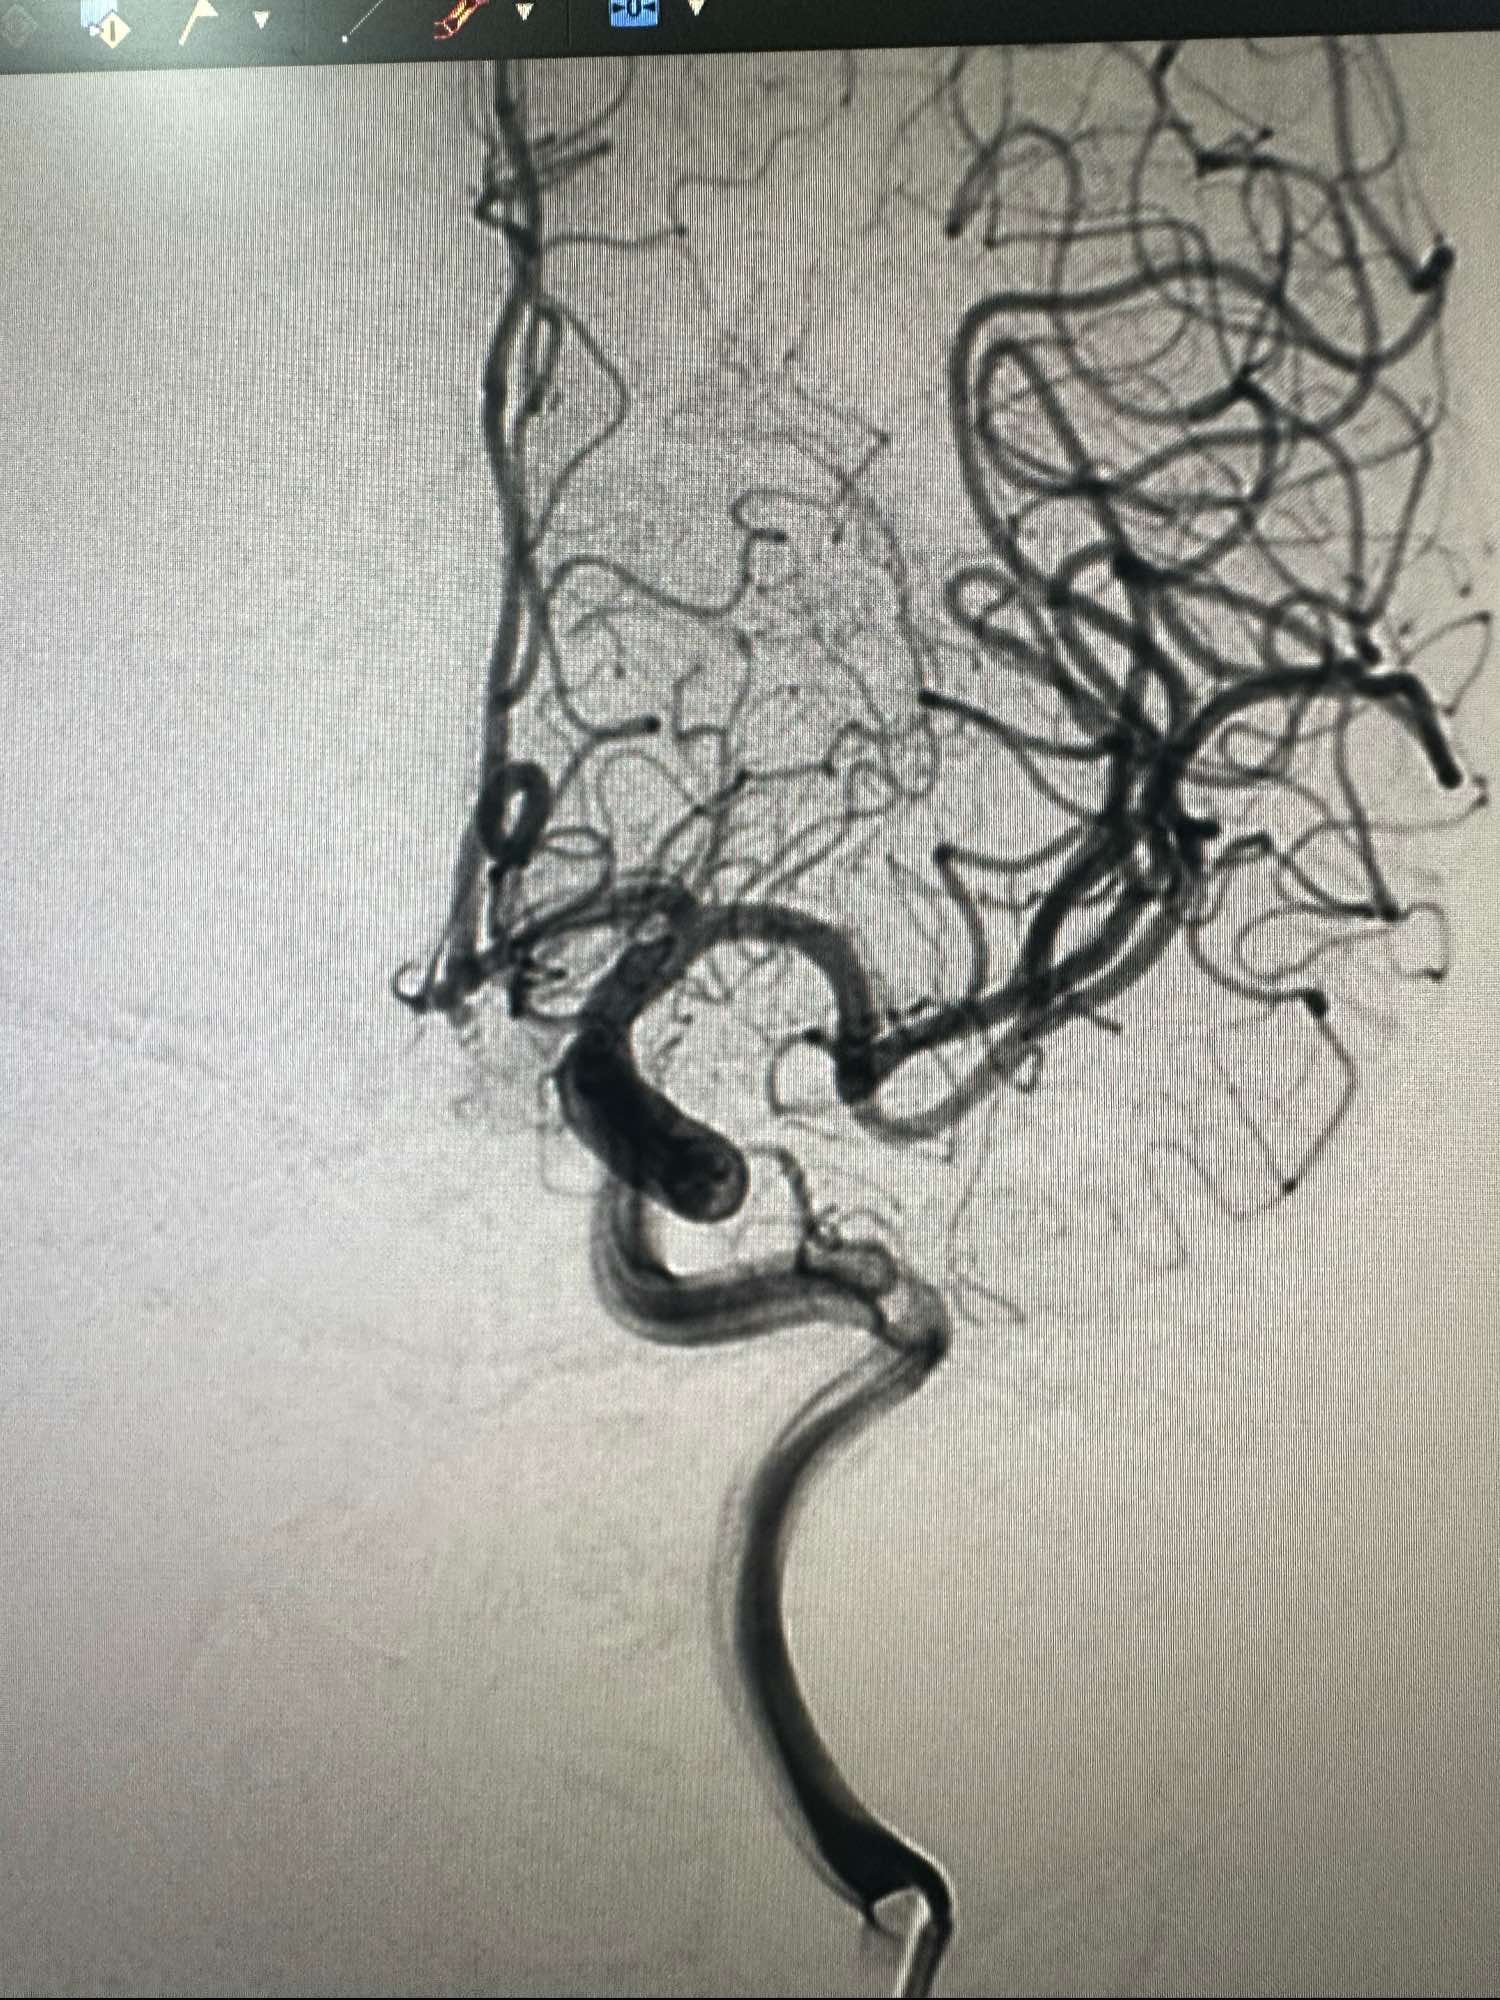

右侧颈内动脉造影正位